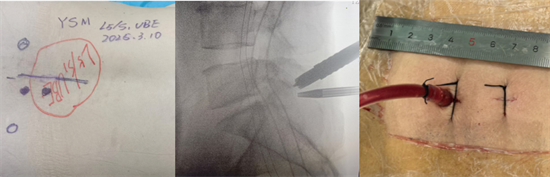

術(shù)中圖片顯示,切口7mm,僅需縫合1針

患者陽(yáng)某某,女,50歲,因反復(fù)腰部疼痛7年加重,并右下肢疼痛麻木半月到衡南縣人民醫(yī)院就診。骨科二區(qū)主任陳軾接診了患者,門(mén)診MRI檢查發(fā)現(xiàn)陽(yáng)女士為典型L5/S1巨大椎間盤(pán)脫出并壓迫神經(jīng)根,保守治療無(wú)效,建議手術(shù)治療。苗驚雷教授與縣醫(yī)院骨科二區(qū)專(zhuān)家團(tuán)隊(duì)為陽(yáng)女士量身定制了無(wú)需內(nèi)固定、創(chuàng)傷更小的UBE微創(chuàng)手術(shù)方案。術(shù)中通過(guò)兩個(gè)7mm的切口,精準(zhǔn)摘除脫出髓核,徹底解除神經(jīng)壓迫。術(shù)后次日,陽(yáng)女士下肢癥狀顯著緩解,已可自主下床活動(dòng)。